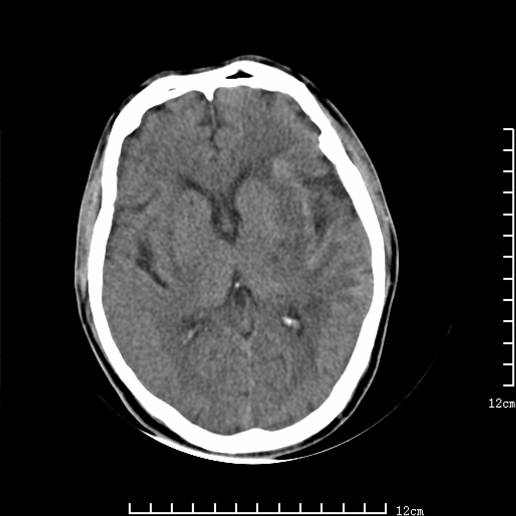

以下图像分别是3月25日凌晨及下午图像、3月27日、4月16日的ct图像。

4月16日

4月16日ct复查:符合出血性脑梗塞表现。

资料齐全,符合脑梗塞溶栓治疗后,血管再通而致的出血性脑梗塞。

支持出血性脑梗塞,可能因血管再通后,再灌注损伤所致。

4月16日ct复查:符合出血性脑梗塞表现